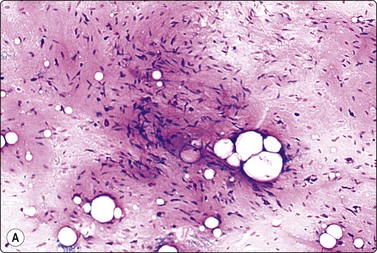

The rare fibrous hamartoma of infancy is a subcutaneous tumor-like mass in the upper arms, shoulder and axillary region. It is composed of a mixture of mature fat, strings of fibrous tissue and primitive mesenchymal cells. The cytologic findings in the few cases published24 are fragments of normal fat mixed with clusters or runs of bland spindle cells. We have had the opportunity to study the smears of two cases (Fig. 15.12).

image

Fig. 15.12 Fibrous hamartoma of infancy

Normal fat cells mixed with clusters or runs of bland spindle cells (MGG, HP).